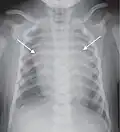

Normal lateral chest radiograph.